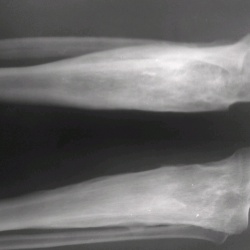

Снимки выполненые при поступлении:       Контроль после оперативной репозиции и фиксации LISS пластиной.